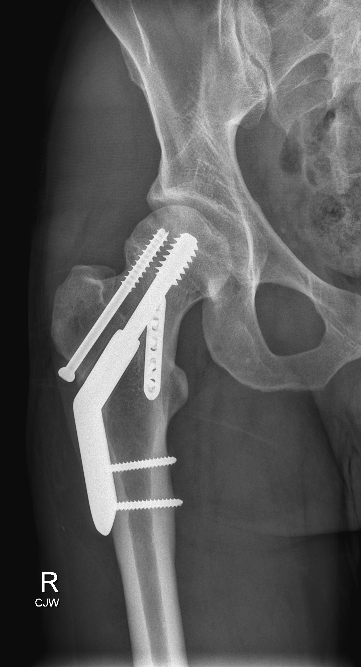

Sports and Trauma

Orthopaedic trauma and sports knee injuries involve damage to the bones, ligaments, tendons, or cartilage of the knee, often from accidents, falls, or high-impact sports. Treatment may include non-surgical management, minimally invasive procedures, or surgery to restore alignment and function.

These injuries are considered when pain, instability, swelling, or loss of mobility limits daily activities or athletic performance. Prompt assessment and treatment are important to prevent long-term complications.

The goals are to reduce pain, restore stability, improve strength and range of motion, and allow return to normal activity or sport.

With modern surgical techniques and rehabilitation protocols, most patients achieve excellent functional recovery, although outcomes depend on the severity of the injury, timing of treatment, and patient factors such as age and activity level.